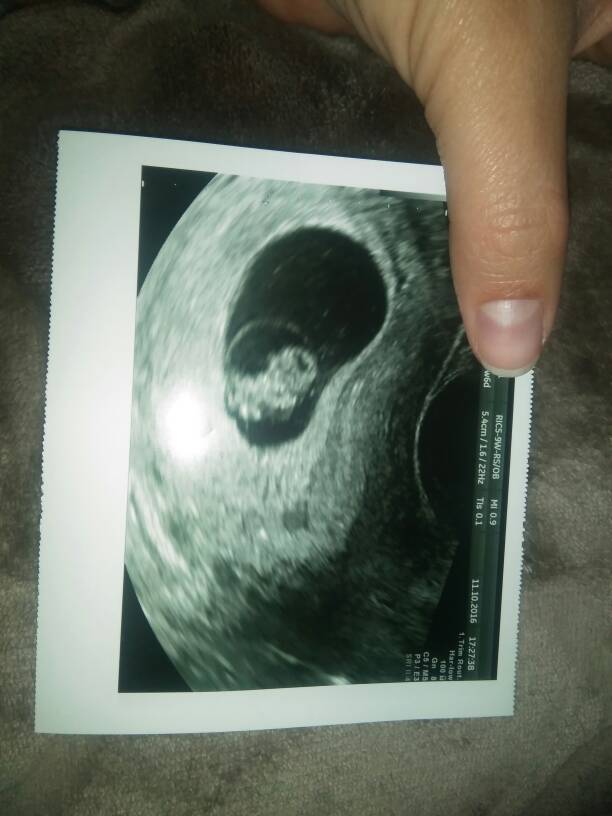

Okej ale slodki ludzik. Wyglada jakby tańczyl[emoji23]. Wreszcie pozytywne wiadomosci w majówkach[emoji7][emoji7][emoji7][emoji7]Zobacz załącznik 777752 Nasz slodziak 7w6d , kochane

Śliczna DzidziaZobacz załącznik 777752 Nasz slodziak 7w6d , kochane